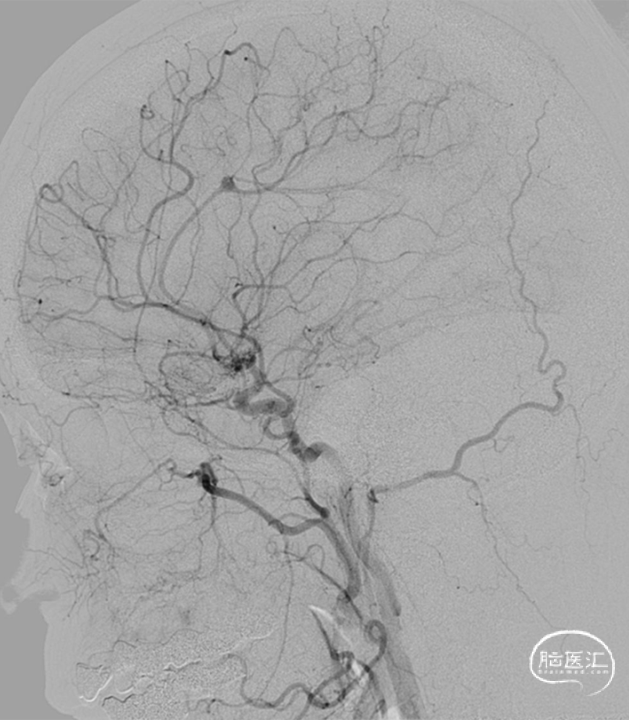

2020.12 造影情况:

2020.12.19 行动脉瘤密网支架植入术,术后影像: